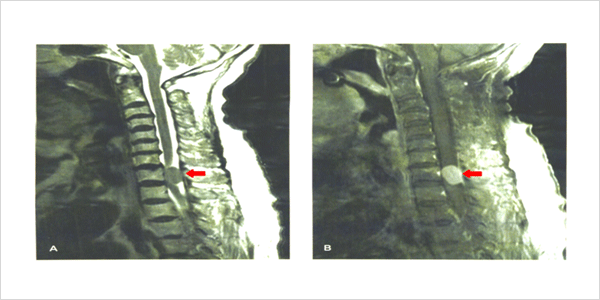

그림설명:

등척추 부위에 발생한 수막종의 자기공명영상 사진입니다. 화살표가 가리키고 있는 둥근 형태의 병변이 수막종으로 조영제를 사용한 우측 사진에서 종양이 밝은 회색으로 관찰되고 있습니다.